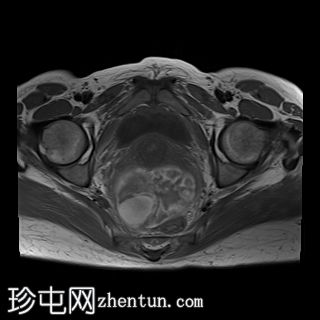

矢状位

T2加权像

1.jpg

左侧卵巢增大、水肿,位置异常,卵泡呈周边排列

左侧卵巢血管扭转,呈漩涡征

上述左侧卵巢增大、水肿、位置异常、卵泡呈周边排列、实质出血的特征提示卵巢扭转伴出血。梗死。